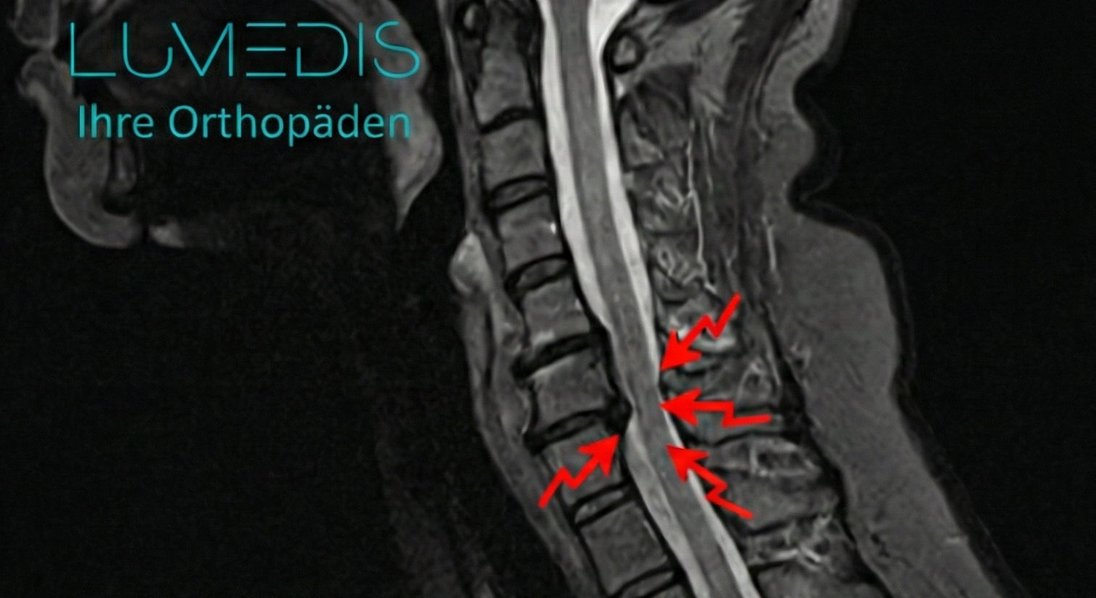

MRT einer Spinalkanalstenose der HWS

MRT einer HWS mit Spinalkanalstenose

MRT der HWS seitlich T2

MRT einer Spinalkanalstenose der HWS C5/C6 (rote Pfeile)